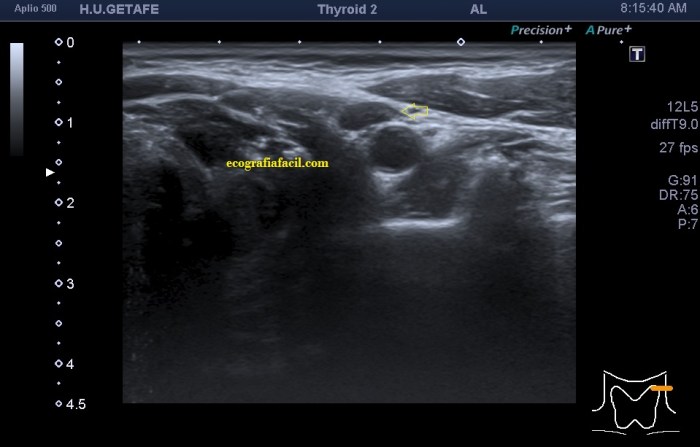

En la 14 un ganglio reactivo con medidas respetadas.

De la imagen 1 a 7 el protocolo habitual, el estudio particular del nódulo con medidas y aplicación del doppler demuestra el aspecto típico del Caballero Blanco.